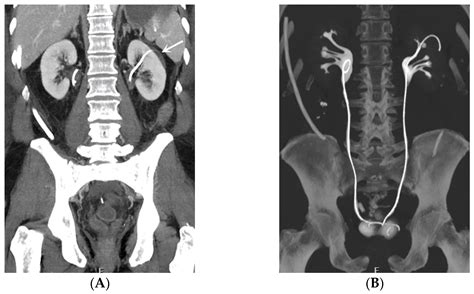

The stent is typically made of medical-grade plastic or silicone, designed to be biocompatible, meaning it can safely remain inside the body for a specific period. It features small curls at both ends—one sitting in the kidney and the other in the bladder—which act as anchors to keep the device from moving out of place. This design is why they are often called "double-J" or "pig-tail" stents.

4. Stent Placement: The stent is threaded over the guidewire and moved into the correct position. Once verified using X-ray imaging (fluoroscopy), the guidewire is removed, leaving the stent in place.